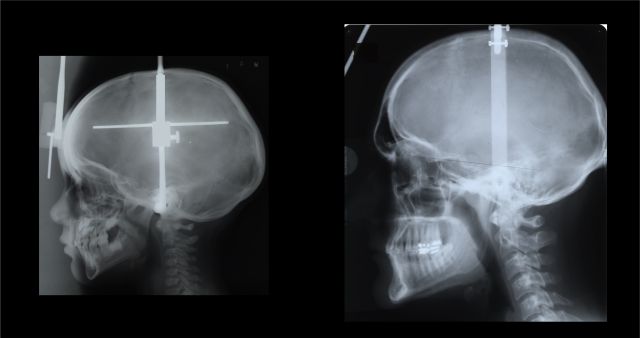

Notice how the modern skull, on the left, has a point at the bottom of the face compared to the Neandethal-era skull on the right. The reason: Only modern humans have chins. Photo illustration by Tim Schoon.

University of Iowa researchers find that we develop chins as our head size increases, from childhood to adulthood. At about 4 years of age (left), we have little indication of a chin, but by our 20s, we have a prominent point at the bottom of our faces.